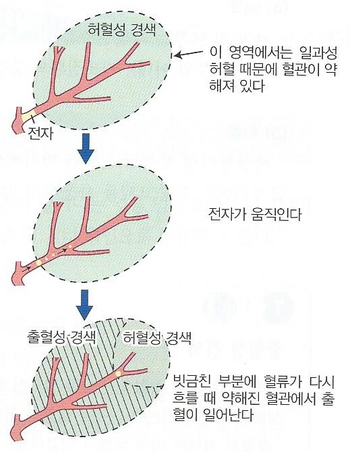

뇌색전증 진행 과정의 후속으로 출혈을 일으키기 쉬운 것도 하나의 특징으로 MRI 검사로 확인할 수 있습니다. 혈전이 초기 위치에서 말초 쪽으로 이동하면 경색 내의 혈관으로 다시 관류되어 출혈이 생기기 쉽습니다. 반면 혈전성 뇌경색으로는 병소가 이동하지 않기 때문에 이러한 후속 출혈은 나타나지 않습니다.뇌색전증에서는 색전의 원인이 될 수 있는 심장 질환을 심전도나 심장 초음파로 찾아내는 것도 필요합니다.